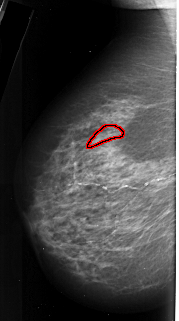

FILE: A_1019_1.LEFT_CC.OVERLAY

TOTAL_ABNORMALITIES 1

ABNORMALITY 1

LESION_TYPE CALCIFICATION TYPE PLEOMORPHIC DISTRIBUTION LINEAR

ASSESSMENT 4

SUBTLETY 3

PATHOLOGY MALIGNANT

TOTAL_OUTLINES 1

BOUNDARY